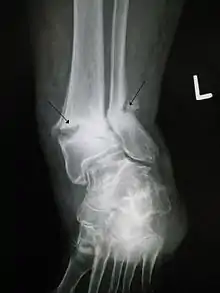

While PEMF therapy is claimed to offer some benefits in the treatment of fractures, the evidence is inconclusive and is insufficient to inform current clinical practice.[4] PEMFs is generally not among the guidelines to treat bone and osteochondral defects. Notwithstanding, there is strong evidence for ELF-PEMF treatment. Pulsed Electromagnetic Fields promote the synthesis of skeletal extracellular matrix. The physiologic process of the response of skeletal cells to PEMF is the synthesis of extracellular matrix structural and signaling molecules in the wound. The result of the signaling processes is to instruct skeletal cells to synthesize structural extracellular matrix and signaling molecules and enhance the ability of skeletal tissues to respond to changing physicochemical environments and biomechanical demands, and facilitate healing.[5] A reduction in time to union and an increase in the percentage of fracture healing in PEMF-stimulated patients compared with controls was reported in fresh tibial fractures,[6] and in femoral neck fractures.[7]